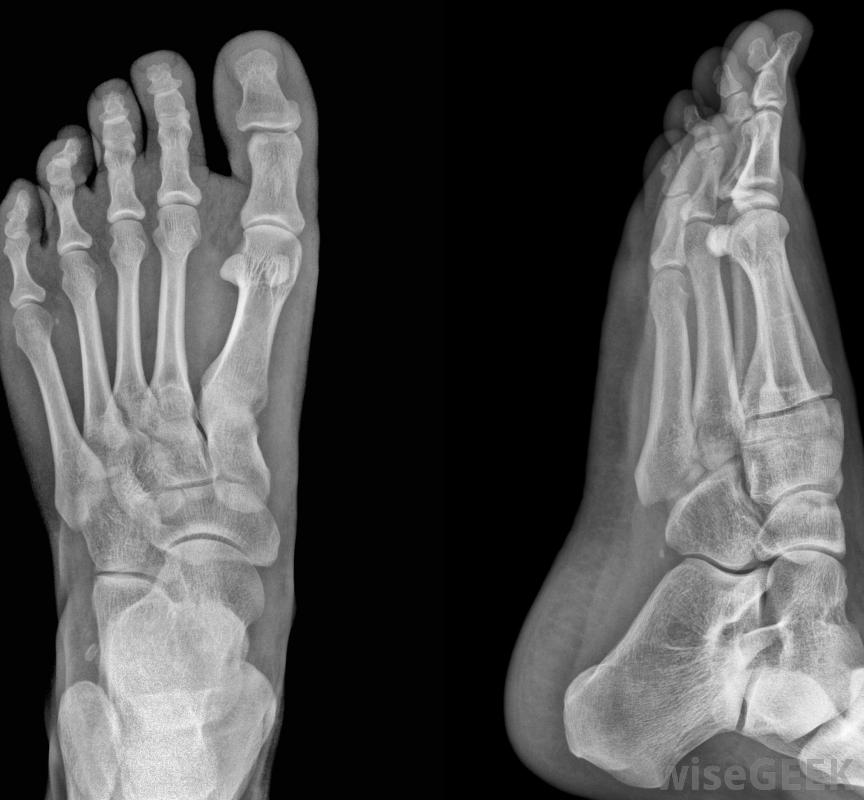

脚趾应力性骨折的症状是什么(Symptoms of a Toe Stress Fracture)?

脚趾应力性骨折最常见的早期症状是受影响的附件有轻微的疼痛和无力。按压在骨折的实际部位也会很痛,虽然没有放射状疼痛。可能没有明显的骨折迹象,虽然可能有瘀伤或肿胀,但脚趾应力性骨折很难发现,因为它的症状与身体其他部位的拉伤和扭伤相似,如果不治疗,疼痛会加剧并持续,甚至可能变得更严重脚趾应力性骨折在x光片上可能看不到,脚趾应力性骨折疼痛加剧的速度取决于损伤的严重程度和程度患者正在移动。久坐的个体可能需要一些时间才能意识到疼痛是骨折。在这种情况下,最明显的症状是疼痛会持续,可能会随着休息而减轻,但永远不要完全消失,那些身体活跃的人通常会注意到疼痛会更快、更剧烈地增加,并且更容易意识到这是一种需要医疗护理的症状冰敷可以缓解脚趾骨折和其他类似的问题起初,骨折会感觉像肌肉拉伤、拉伤或扭伤。这些情况和骨折的主要区别在于,它们不会像骨骼中的细线裂开那样最终使人丧失能力。脚趾骨折晚期最终会变得疼痛不堪,无法承受任何重量脚趾应力骨折很难诊断,因为患者通常;脚趾部疼痛和疼痛难以察觉,他们可能无法在x光片上确认,有时裂口很小,直到愈合过程顺利进行时才会出现。在这些情况下,核磁共振成像或CAT扫描可以确认症状是否来自骨折足趾骨折可能导致足部无力。对于足趾应力性骨折有几种误解,可能会导致患者失去体征。其中最常见的是一个有骨折的人不能移动受影响的脚趾,尽管该区域的神经和肌肉实际上仍然可以活动。至少在受伤的早期阶段,也有可能在骨折上行走。另一个常见的误解是,必须有可见的骨折外部证据,例如该区域的瘀伤或肿胀虽然某些可见的迹象是可能的,但并不总是出现的。脚趾应力性骨折可以通过将受伤的脚趾绑在相邻的脚趾上来治疗轻度疼痛和虚弱可能是脚趾应力性骨折的症状。久坐的人可能需要很长时间才能注意到脚趾骨折。处理脚趾骨折的人可以使用拐杖帮助愈合可能需要进行CAT扫描,以检测到细微的脚趾骨折。